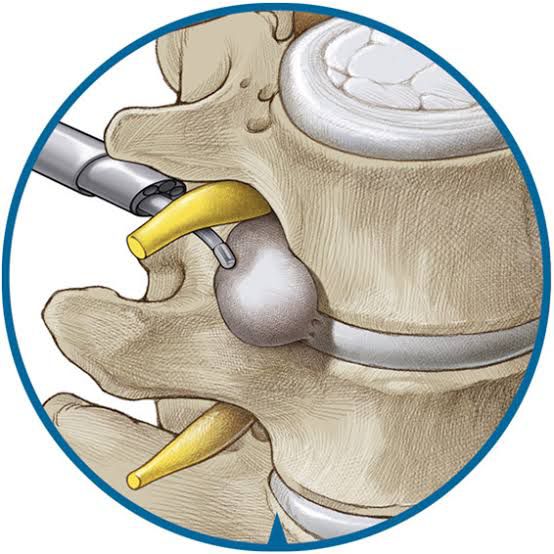

Recientemente fui acreedor al Segundo Lugar Internacional en el

Needle Spine Challenge

de cirugía endoscópica de mínima invasión en columna.

Congreso europeo de columnaEurospine

, Finlandia 2019 -

Adiestramiento en cirugía de columna de mínima invasión en

4th Annual Johns Hopkins Spine Workshop 2016

- Estoy altamente entrenado para realizar abordajes de mínima invasión en cráneo y columna.

Masculino de 82 años, operado de conducto lumbar estrecho.

El paciente se encuentra dando testimonio antes de las 24 hrs post operatorio.